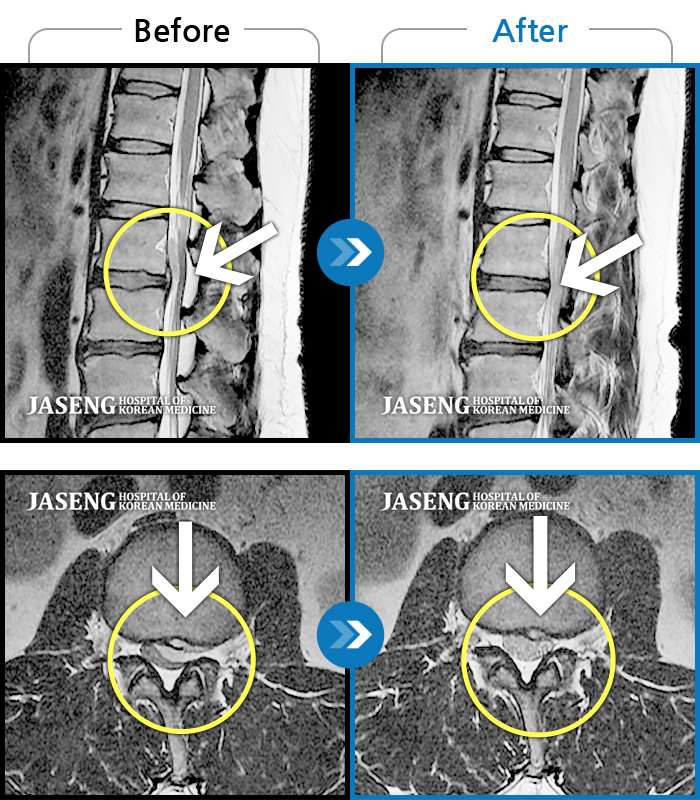

Before

After

환자에게 사전 동의를 받아 동일 조건에서 촬영되었습니다.

개인에 따라 치료 후 부작용이 발생할 수 있으니 의료진과 상담 후 치료를 진행하시기 바랍니다.

처음 내원 시 좌측 둔부 하지 바깥쪽의 심한 통증으로 내원하셨습니다.